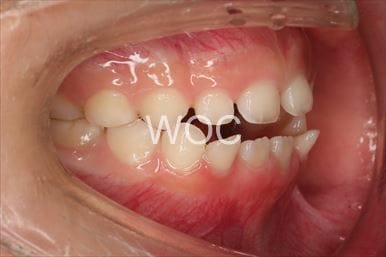

叢生

治療前1

治療前2

治療前3

治療前4

治療前5

- 年齢:7歳9ヶ月

- 主訴:スペースがない、デコボコしている

- 診断名:叢生、上顎前突、過蓋咬合

- 装置:可撤式拡大装置、機能的矯正装置

- 期間:4年1ヶ月 ※

- 費用:基本矯正料金:380,000円